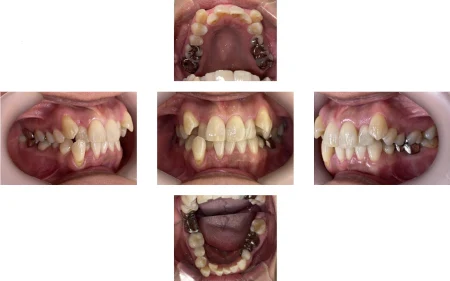

50代女性「前歯がガタガタで笑えない」マウスピース型矯正装置「インビザラインフル」で、非抜歯にて歯並びと噛み合わせを治療し、見た目を改善した症例

「前歯のガタガタがひどく、人前で笑えない。歯を抜かずに治したい」とご相談いただきました。

拝見すると、上下左右の前歯12本(中切歯/1番・側切歯/2番・犬歯/3番)が、デコボコに生えている状態の「叢生(そうせい)」でした。

患者様のご希望に沿い、非抜歯で歯並びを整えるためにマウスピース型矯正装置の「インビザラインフル」を選択しました。